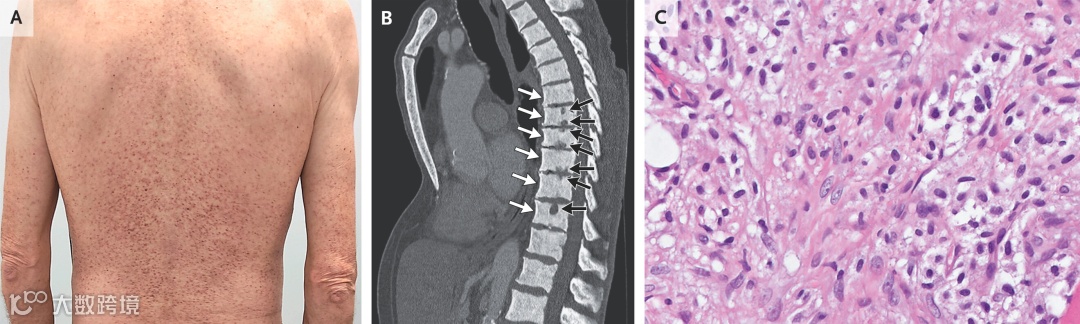

体格检查发现躯干、手臂和双腿上有斑丘疹性皮疹 (图1A)。

腹部和盆腔CT检查显示胸椎椎体骨硬化(图1B,白箭,矢状位)以及终板侵蚀(图1B,黑箭)。未见肝脾肿大。

图1. 患者临床、影像及病理图片

皮肤活检提示肥大细胞浸润。骨髓活检显示圆形与梭形细胞形成的黏聚团块,伴致密染色质、嗜酸性胞质以及明显的胶原纤维化。免疫组化结果为CD25和CD117(c-Kit)阳性。分子检测发现KIT基因功能获得性D816V突变。

系统性肥大细胞增多症是一种罕见的造血干细胞克隆性疾病,以肥大细胞在骨髓、皮肤、骨骼和胃肠道等组织的浸润为特征。其影像学特点是骨硬化与骨侵蚀并存,实验室可见血清类胰蛋白酶显著升高,病理和分子学证据确立诊断。